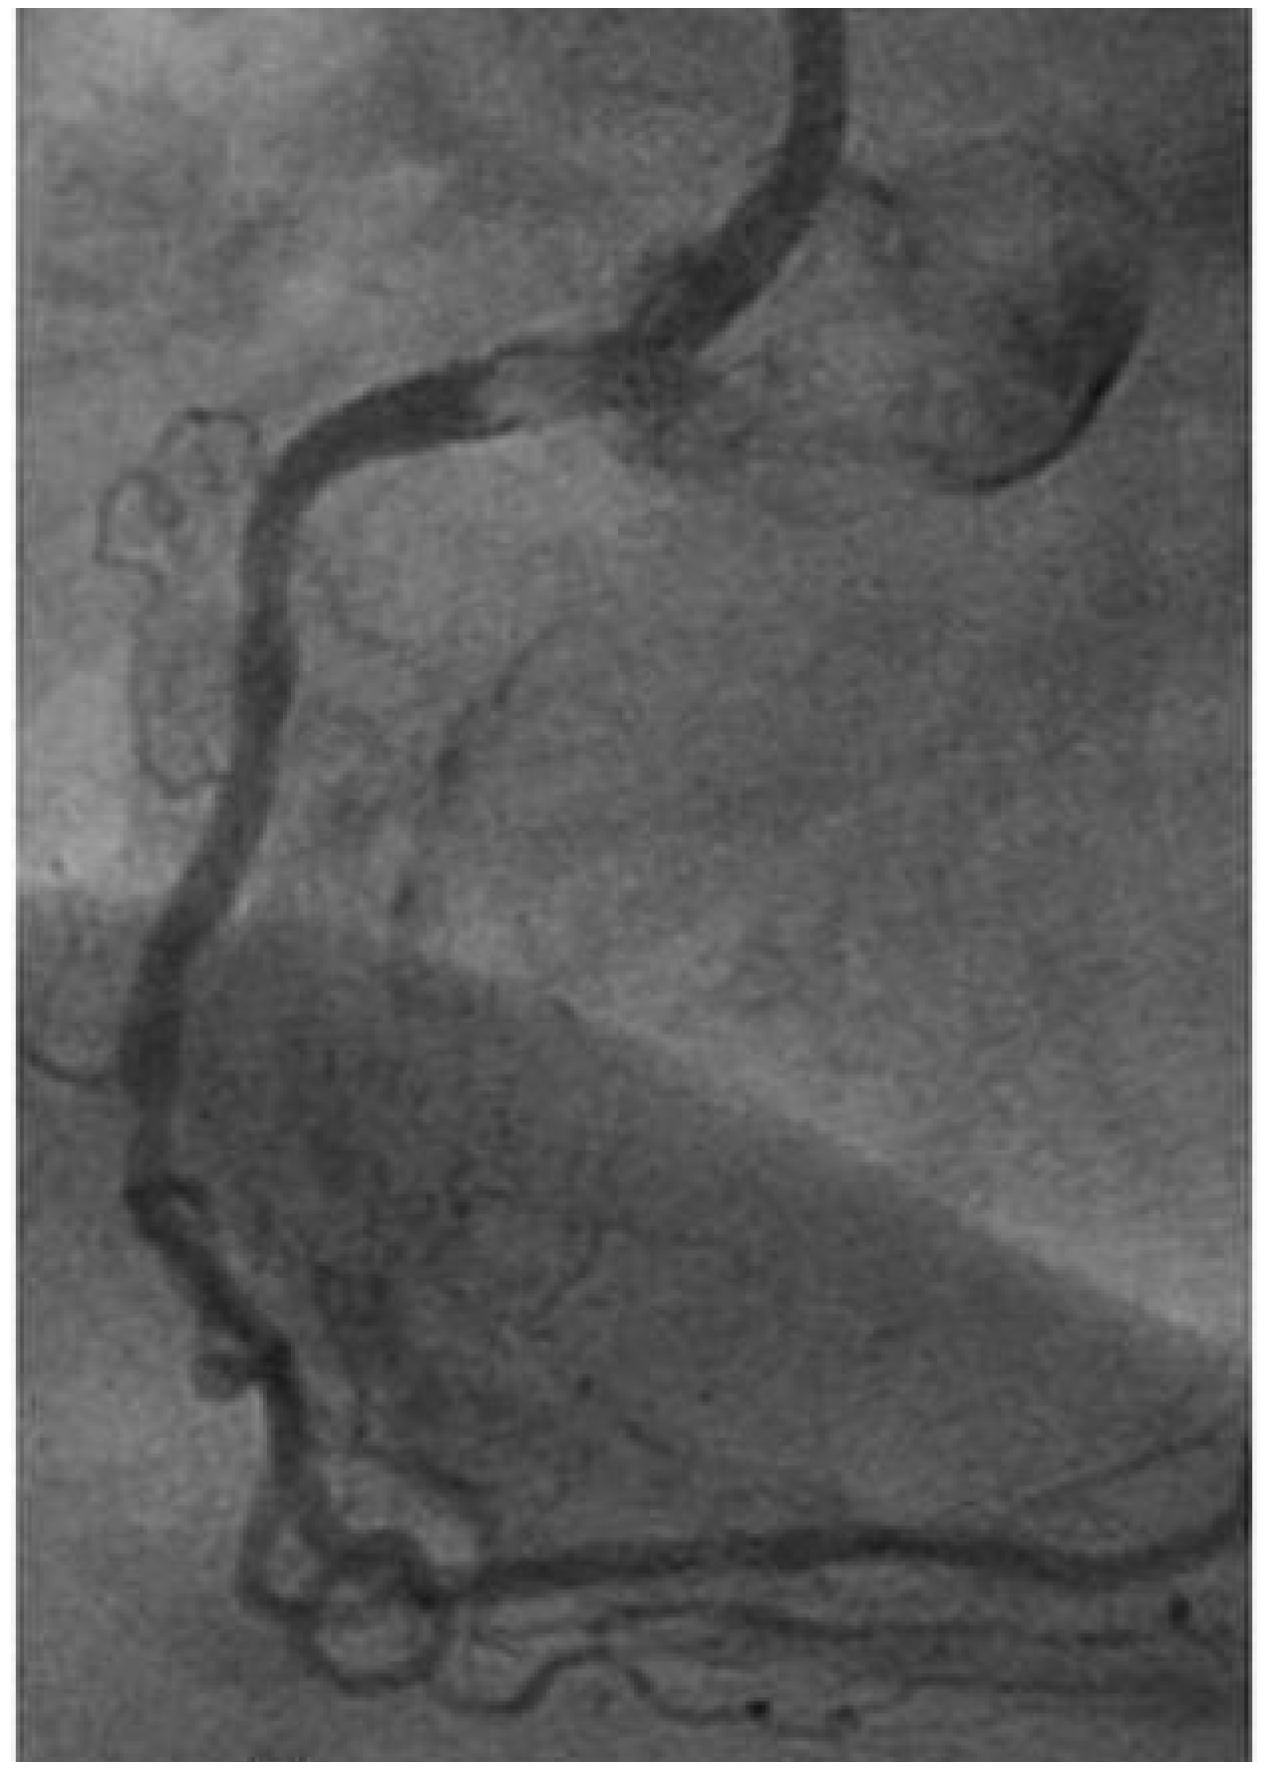

Case report 3: fibroelastoma

- Erdös, G.; Stalder, M.; Basciani, R.; Gugger, M.; Carrel, T.; Eberle, B. An Uncommon Cause of Coronary Artery Ostial Obstruction: Papillary Fibroelastoma. Echocardiography. 2010, 27, 337–340. [Google Scholar] [CrossRef] [PubMed]

- Yerebakan, C.; Liebold, A.; Steinhoff, G.; Skrabal, C.A. Papillary fibroelastoma of the aortic wall with partial occlusion of the right coronary ostium. Ann Thorac Surg. 2009, 87, 1953–1954. [Google Scholar] [CrossRef] [PubMed]